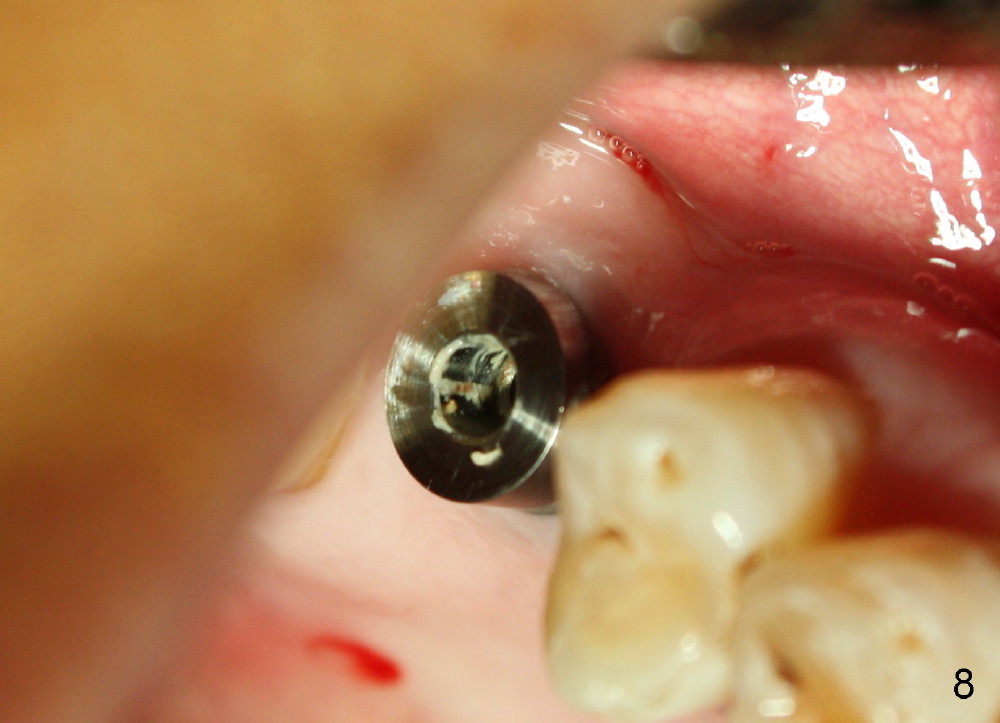

Six months and a half later, the socket appears to be empty (Fig.5) with apparently buccal plate collapse (as indicated by inset in Fig.5). The bony ridge is measured to be ~ 5 mm buccolingually using bone gauge. Osteotomy forms by bone expansion technique. In short, #15 blade is used to split the ridge (slightly lingual), followed by bone scalpels 4,5, and 6 mm, bone blades 4, 5.5 and 7.5 mm, and round tapered osteotomes 2, 3, 4 and 5 mm (Tatum Surgical). The depth is approximately 11 mm. When the last osteotome (4.5 mm round blunt) is used, it deviates too much lingually. A surgical curet is used to explore the osteotomy site. The bony wall appears to be intact except lingual. A 6x11 mm tapered tap is inserted with some resistance (Fig.6). In contrast it is difficult to engage 5.8 mm round tap into the osteotomy site. A 6x11 mm tapered implant is placed with insertion torque 40 Ncm (Fig.7). Amoxicillin is prescribed. The patient is doing fine postop, although the implant is not stable with mild tenderness. Six month post-implantation, the implant appears to have been descended (Fig.8,9, compare to Fig.7).

Following local anesthesia, the failing implant is removed without resistance. The sinus floor is present. The lateral walls are intact, although probably short. A series of rounded tapered osteotomes (2-5 mm in diameter) are used for sinus lift at the depth of 14 mm. A 4.5x14 mm tap is inserted (Fig.10). One more carpule of Lidocaine is administered. A 6x14 mm implant is placed with torque more than 60 Ncm without additional bone graft (Fig.11). A 6-month postop PA confirms osteointegration (Fig.12). An abutment is placed (Fig.13) for a definitive crown (Fig.14). PA taken 6 months post cementation shows that bone density mesial to the implant increases (Fig.15 <).